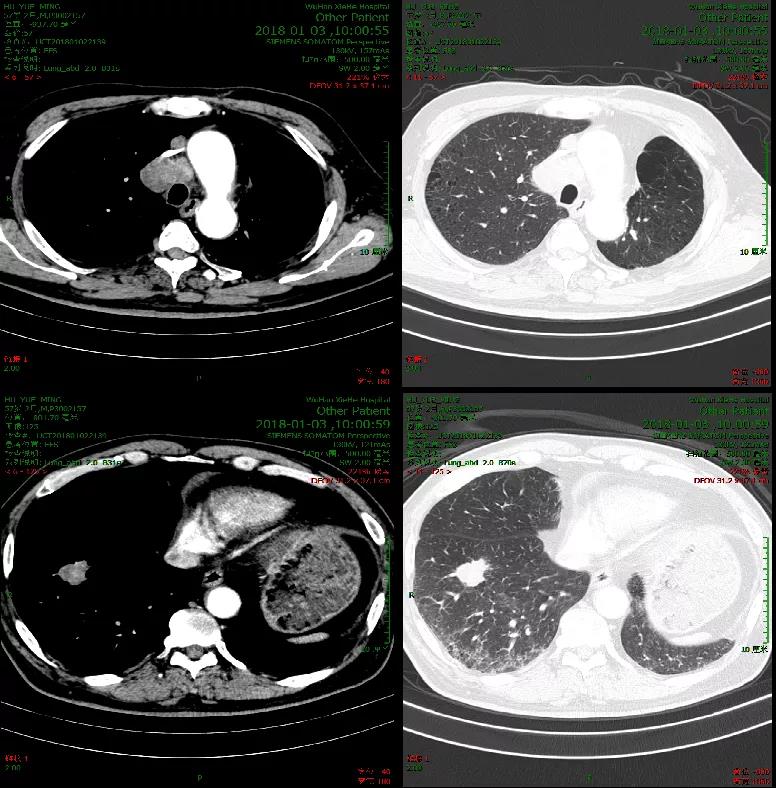

影像学基线检查:胸部CT,2018年1月3日(图1)。

2018年3月第一次疗效评估即达到PR,2018年6月开始行维持治疗,至2020年1月维持治疗结束。2020年5月随访结果显示患者仍然保持病情稳定,PFS已达28个月(图3)。